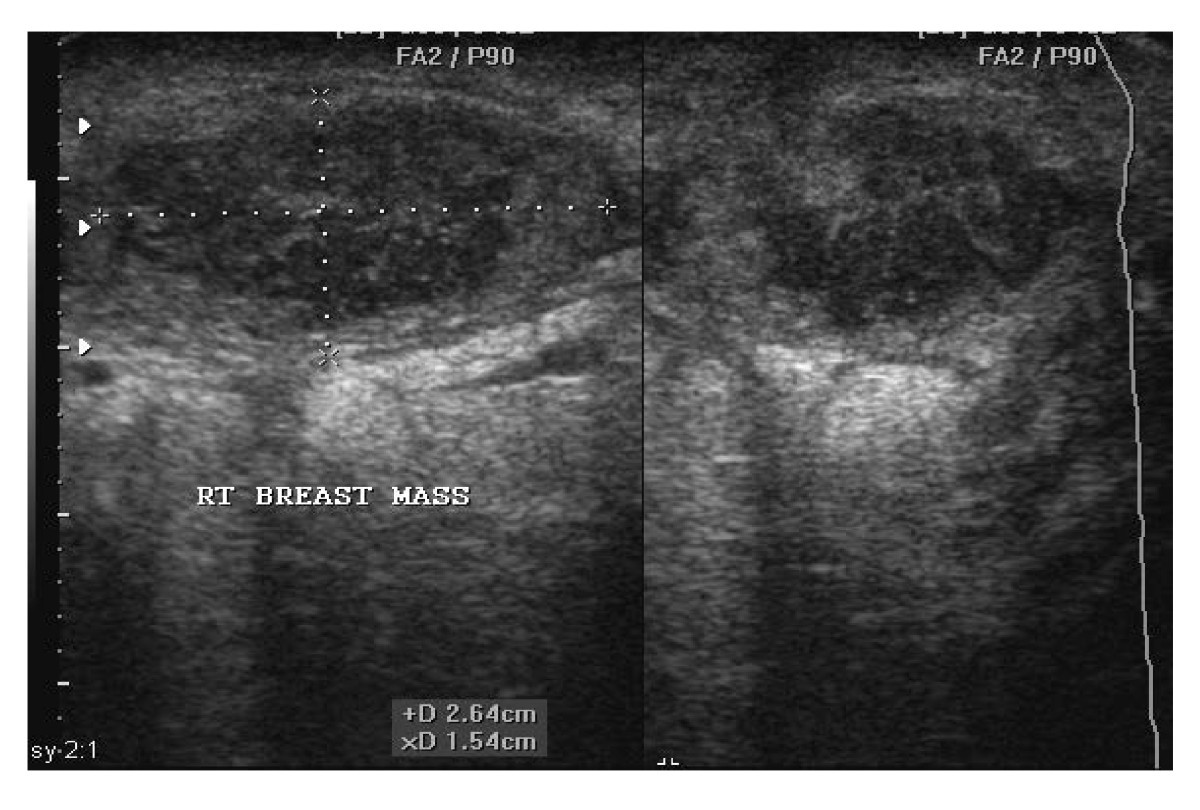

Breast abscess ultrasound wikidoc Abscess Nipple It is a common problem in breastfeeding or. a subareolar abscess is commonly referred to as a breast abscess. An infection in the breast can lead to a breast abscess, which is a common condition in lactating females. This blockage can lead to an infection under. breast abscess refers to an inflammation (swelling, redness) that results in such. Abscess Nipple.